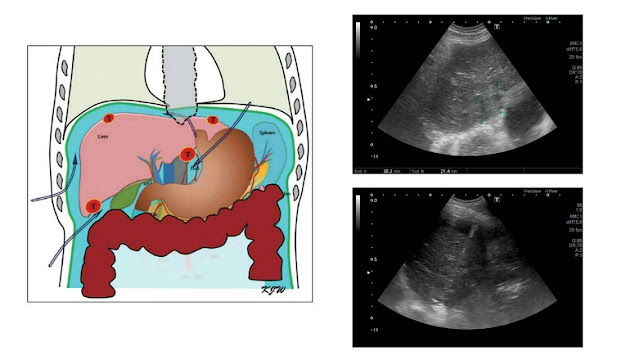

湯昇曄醫師說,肝癌電燒的步驟是先用超音波定位肝臟腫瘤的位置,並且在超音波導引之下,把電燒針放至預作電燒的地方,並根據腫瘤的大小及位置,選用單支電燒針或是多支電燒針同時進行電燒,最大可以達到6公分甚至更大的完整電燒範圍,足夠大的電燒範圍就能治癒早期肝癌,對於一些困難作電燒的位置,譬如腫瘤靠近肺部、胃腸或心臟,也能藉由注射人工腹水,避免傷害到這些器官;當然電燒的過程中多少會感到疼痛及不舒服,所以會給予注射止痛藥、局部麻醉藥及低劑量的鎮定劑,來減少治療過程中的不舒服,大部分的病人都能順利且完整的接受電燒的治療過程。